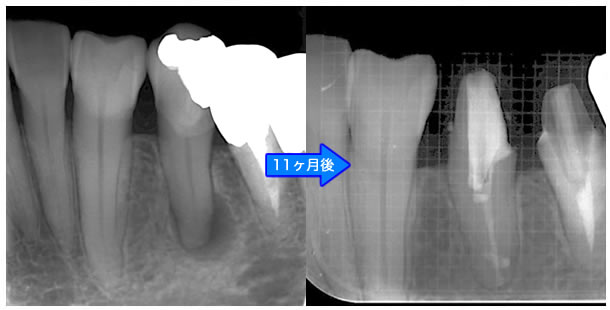

頬側骨壁の根尖部まで無くなっています。

MTA根充後11ヶ月で透過像が消失し、根尖部が正常化しました。

| 治療説明 | 左下第一小臼歯の頬側根尖部からの排膿、痛みはないそうです。X線画像では根尖部に透過像を認められます。 頬側の骨も失われており、歯髄が死んだことが原因と考えられます。修復物を除去後根管治療を行い、根管充填後、透過像は消失、頬側骨も再生されていました。 |